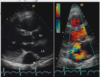

Name of this anomaly and explain

D-TGA or D loop. The LV and RV are in a normal location but the PA is conected to the LV and the Ao is connected to the RV. so the grear Arteries are parallel to each other In D-TGA the aorta is anterior to the Pulmonary Morfologycal RV is on the Right